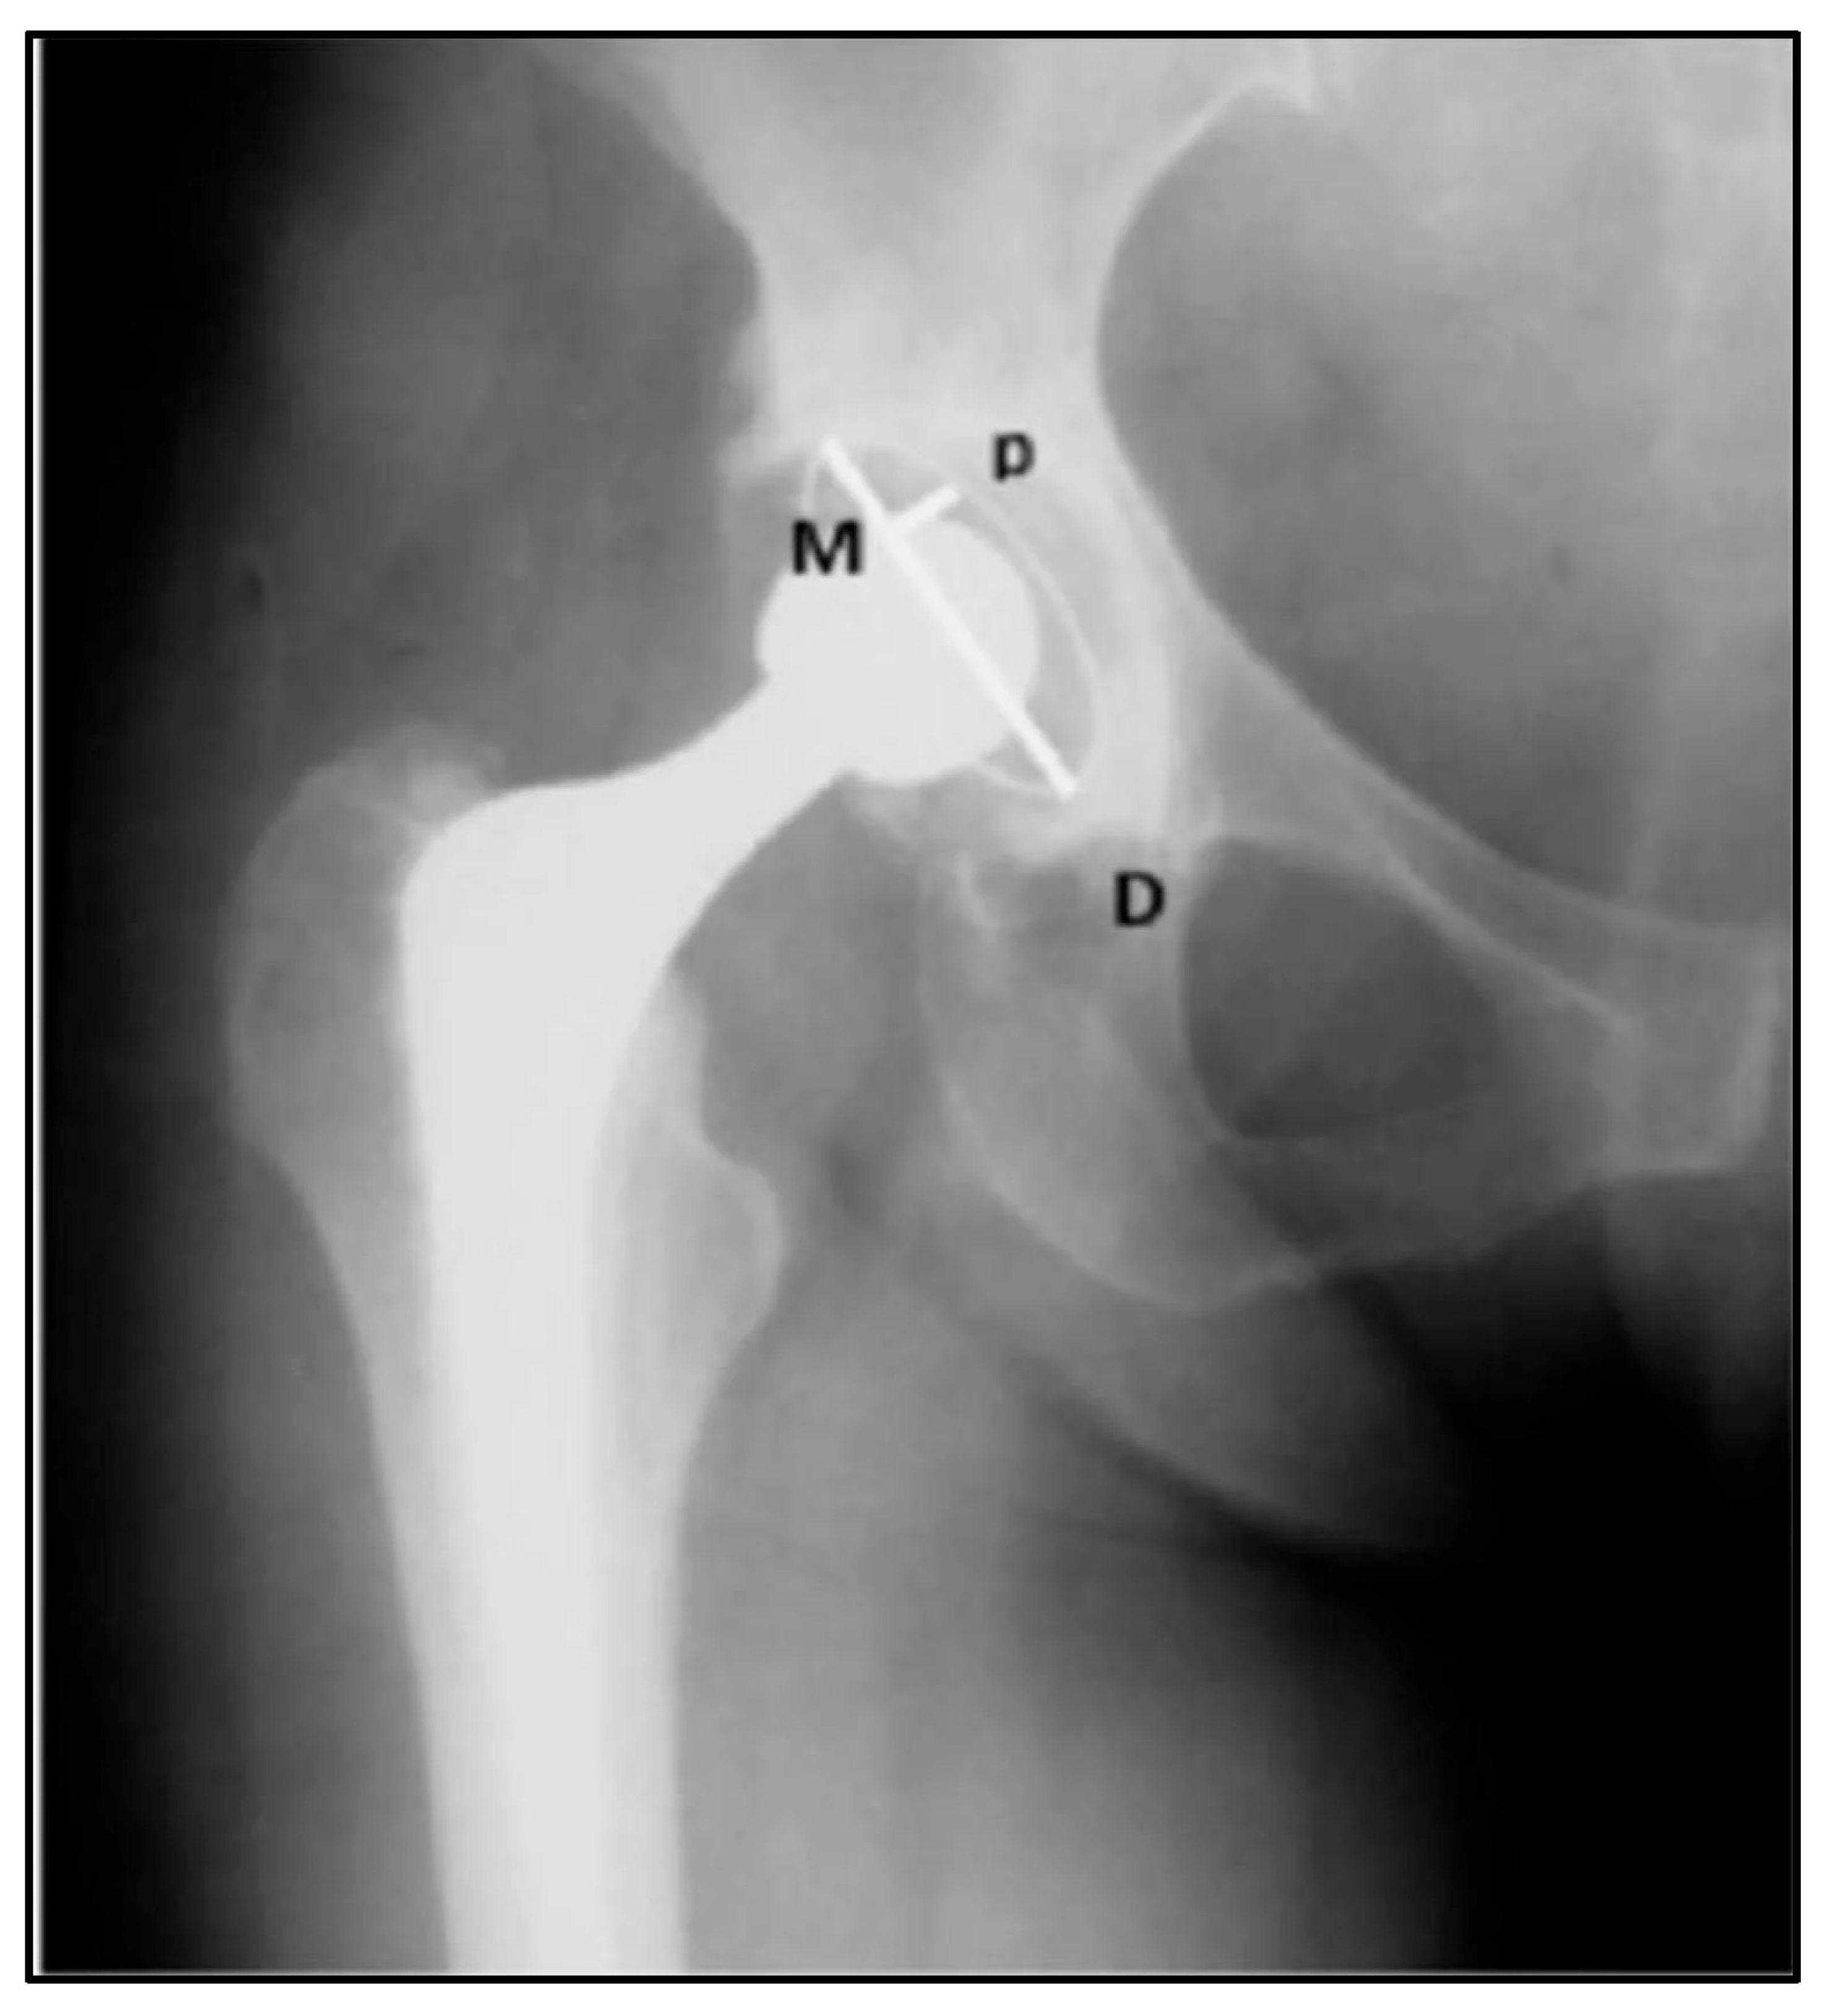

Figure 3.

Radiographic areas of acetabular displacement, proposed by DeLee and Charnley, represented in the angle of lines M and D (1976) [14] © MDPI 2023.